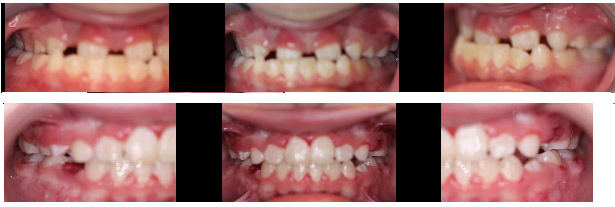

PROBLEMS CAUGHT EARLY CAN PREVENT EVEN BIGGER PROBLEMS: FUTURE SURGERY, EXTRACTIONS, AND EXPENSIVE/COMPLICATED ORTHODONTIC CARE!